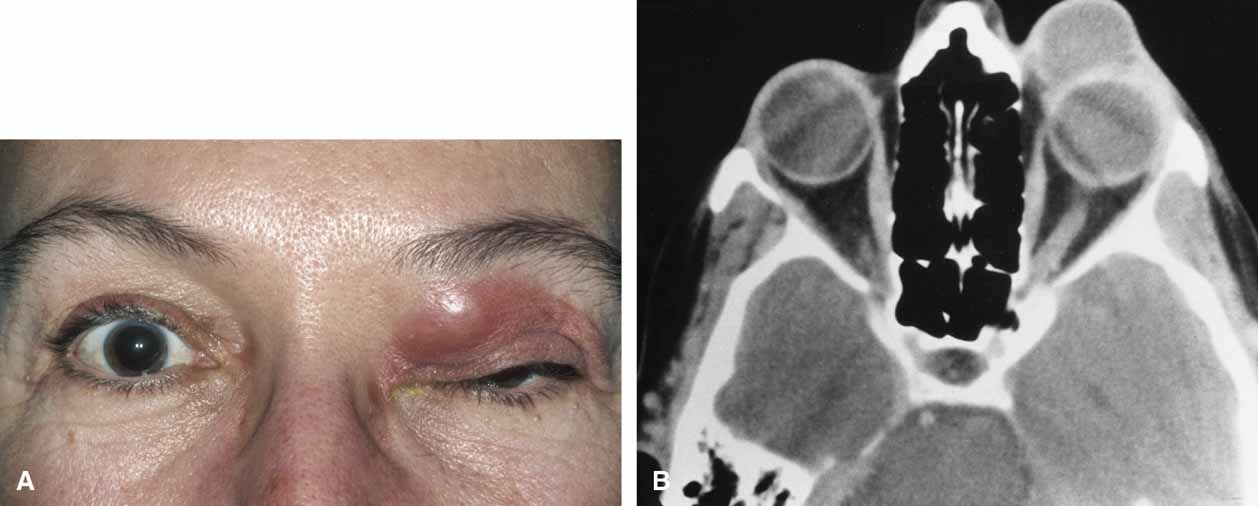

Hematic cysts are uncommon, and the clinical history and ophthalmic findings rarely are diagnostic.48–50 Mass effect with proptosis, globe displacement, and motility disturbance are common with chronic hematic cysts. Spontaneous eyelid ecchymosis and edema may suggest this diagnosis (Fig. 10). In acute hematic cysts, optic nerve signs may be present, including decreased vision, afferent pupillary defect, and choroidal folds.51

Fig. 10 A. Spontaneous periorbital ecchymosis and diplopia in a man who had undergone a left orbital blowout fracture 5 years previously suggest the presence of a hematic cyst. B. Computed tomogram shows the left globe and a previously placed Silastic plate displaced superiorly by the expanding hematic cyst in the floor of the left orbit.